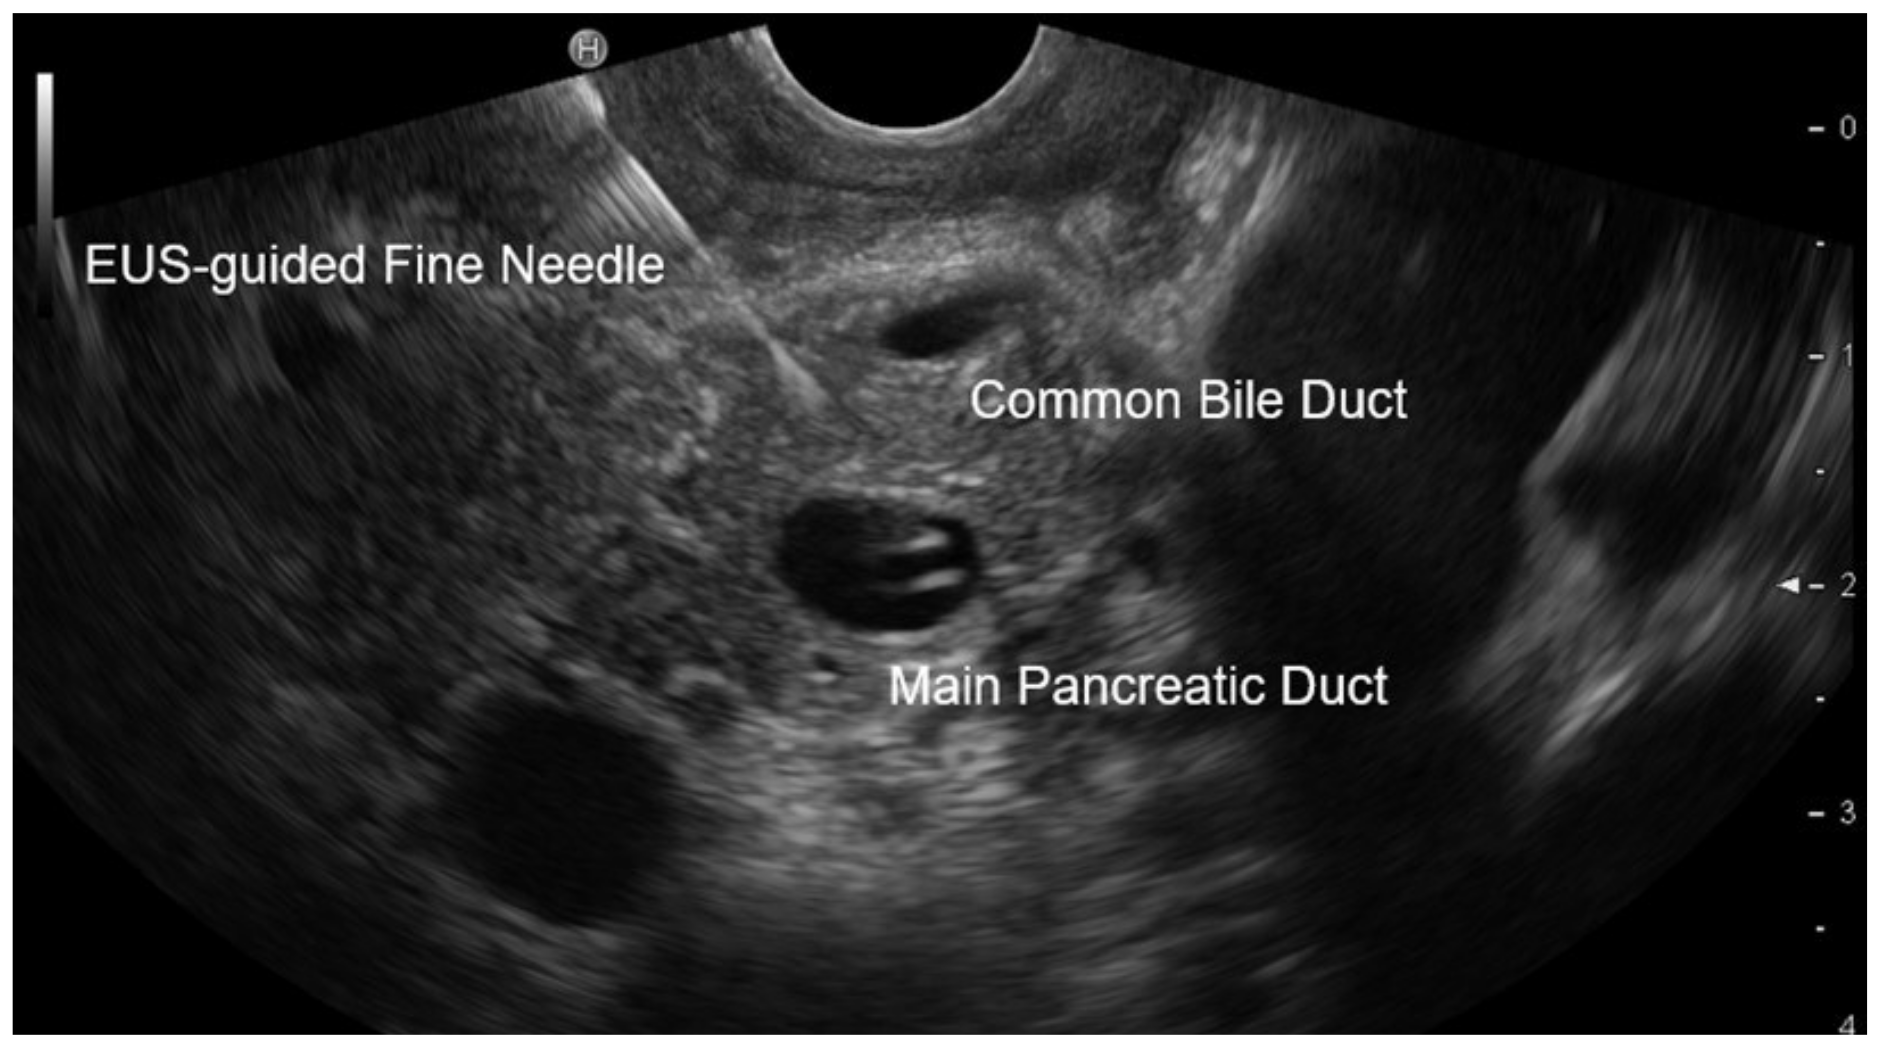

2.4. EUS Procedure